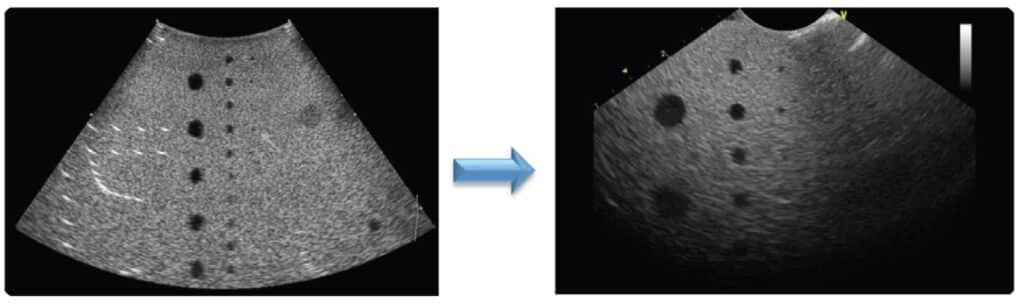

When a lens failure has occurred (or is progressing), sonographers may complain of poor or reduced penetration, regional shadowing in the image, and even no image whatsoever. From a QC perspective, you would see changes in uniformity over-time as well as changes in penetration and resolution over-time. What once was, would no longer be achievable.